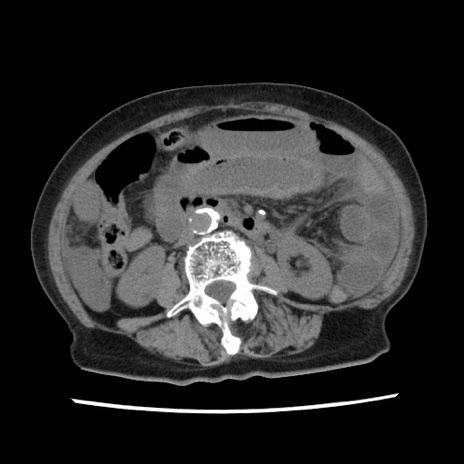

症例1(横断像)

【症例】80歳代女性

【主訴】腹痛

【現病歴】8時間前から腹痛あり来院。

【既往歴】糖尿病、脂質異常症、子宮体癌にて子宮全摘術

【身体所見】意識清明・会話良好だが腹痛で苦悶様、全腹部にわたって反跳痛と圧痛あり

【データ】WBC 13600、CRP 0.14、LDH 224、CK 90